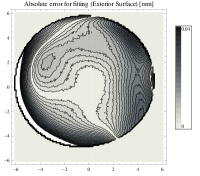

In the case of surface of revolution, normal vector lies in the meridional plane so is the distance along the normal vector from the surface point to the axis of revolution. The absolute error in fitting calculated for our is depicted on Fig. 4. Mean errors are approximately and for interior and exterior surfaces respecively.